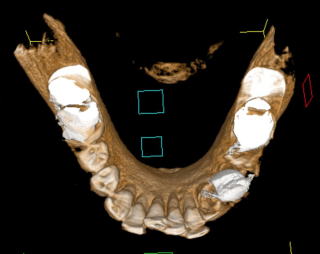

である。開業当初から当診療システムで38年間口腔管理をしている。Panorama、CTなどレントゲンを介しての顎骨・歯槽骨の形態・骨

量などを観察したもので、歯槽骨の吸収状態から診ても、ほぼ二十歳代に相当するように思われる。過去の論文を見ても、口腔内写真

■Volume Rendering(CT)

(図15)2015年7月27日、83歳。高年齢と残存歯数ばかりが問題視されているが、歯槽骨の状態、歯肉、Pocketの状態を含めた歯周病を評価すべきである

歯周病治療38年経過:83歳(女性)残存歯数28本